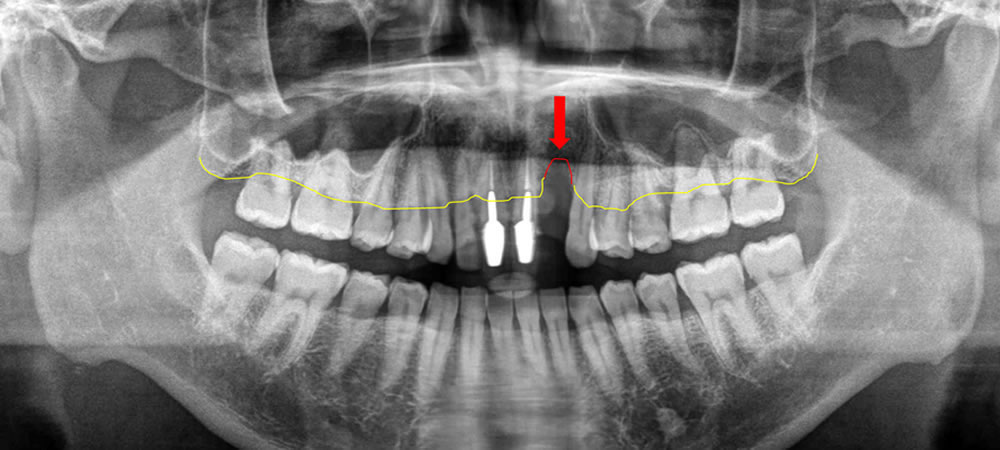

【初診時パノラマX線写真/デンタルX線写真】

各レントゲン写真から虫歯の有無、歯を支える骨の状態を細かな部分までチェックします。抜け落ちた歯の部分には骨が陥没している様子が見えました。虫歯はないようですが、周囲の歯も歯周病により支える骨が全体的に溶けている様子が確認できました。そのため、欠損部の咬み合わせを回復する前に歯周病治療を行い、口腔内の環境を改善する治療計画を立てました。